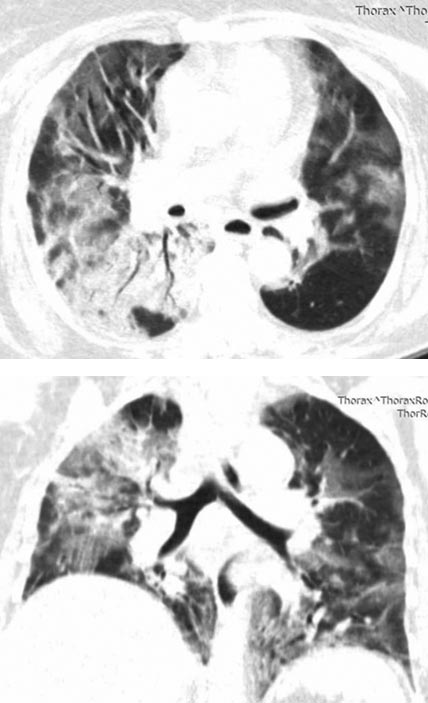

В поликлинику обратилась на 5-й день, была направлена на рентгенографию органов грудной клетки, выявлена двусторонняя пневмония. На 6-й день болезни в связи с дальнейшим ухудшением общего самочувствия бригадой скорой медицинской помощи была доставлена и госпитализирована в провизорный инфекционный госпиталь. При РКТ верифицированы признаки двусторонних интерстициальных изменений лёгких с участками «матового стекла», соответствующие вирусной пневмонии с объёмом поражения КТ 2 (рис. 1).

Рис. 1. Рентгеновская компьютерная томограмма при госпитализации (КТ 2)